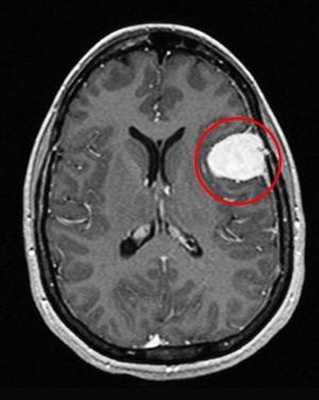

Отметим его красной окружностью. Визуально оно представляет собой узел, неоднородный по окраске и отличающийся от серого и белого вещества головного мозга. В таких случаях, чтобы точно определить границы опухоли и определить её тип исследование повторяют с контрастом. Введение контрастного препарата в кровь через локтевую вену приводит к накоплению контрастного вещества в тканях опухоли - нормальные здоровые ткани его практически не накапливают. И мы получаем следующую картину, показанную на рисунке справа. Яркая окраска опухоли соответствует накопленному контрасту - теперь можно не только сказать, где опухоль, но и примерно определить, что это доброкачественная опухоль, так как она имеет четкие границы (злокачественные опухоли прорастают окружающие ткани, из-за чего границы будут размытыми и не такими четкими).